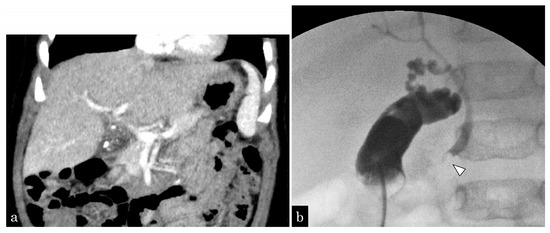

3.1.3. Patient 3

3.1.4. Patient 4